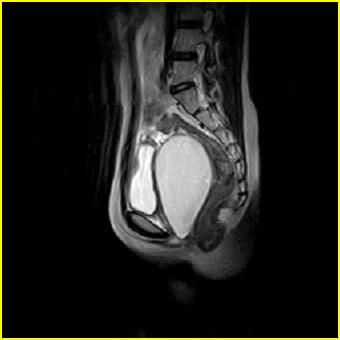

女、15岁、下腹疼痛2天,排尿困难1天。查体:处女膜闭锁,距处女膜约4至5cm处扪及一约5cm直径的圆形包块,张力较高,触痛明显、欠活动。b超提示子宫增大伴宫内增强回声团。

影像意见:子宫直肠陷凹积血。

更正影像意见:阴道积血。

处女膜闭锁,阴道积血

处女膜闭锁,阴道积血,子宫积血.

阴道积血,子宫积血.

子宫及阴道积血。

处女膜闭锁,伴子宫及阴道积血.